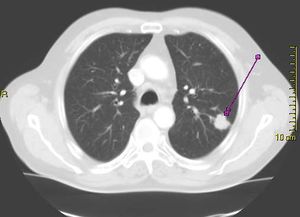

| Cross section of a human lung. The white area in the upper lobe is cancer; the black areas are discoloration due to smoking. | |

- الأشعة السينية

- مسح مقطعي (الأشعة المقطعية)